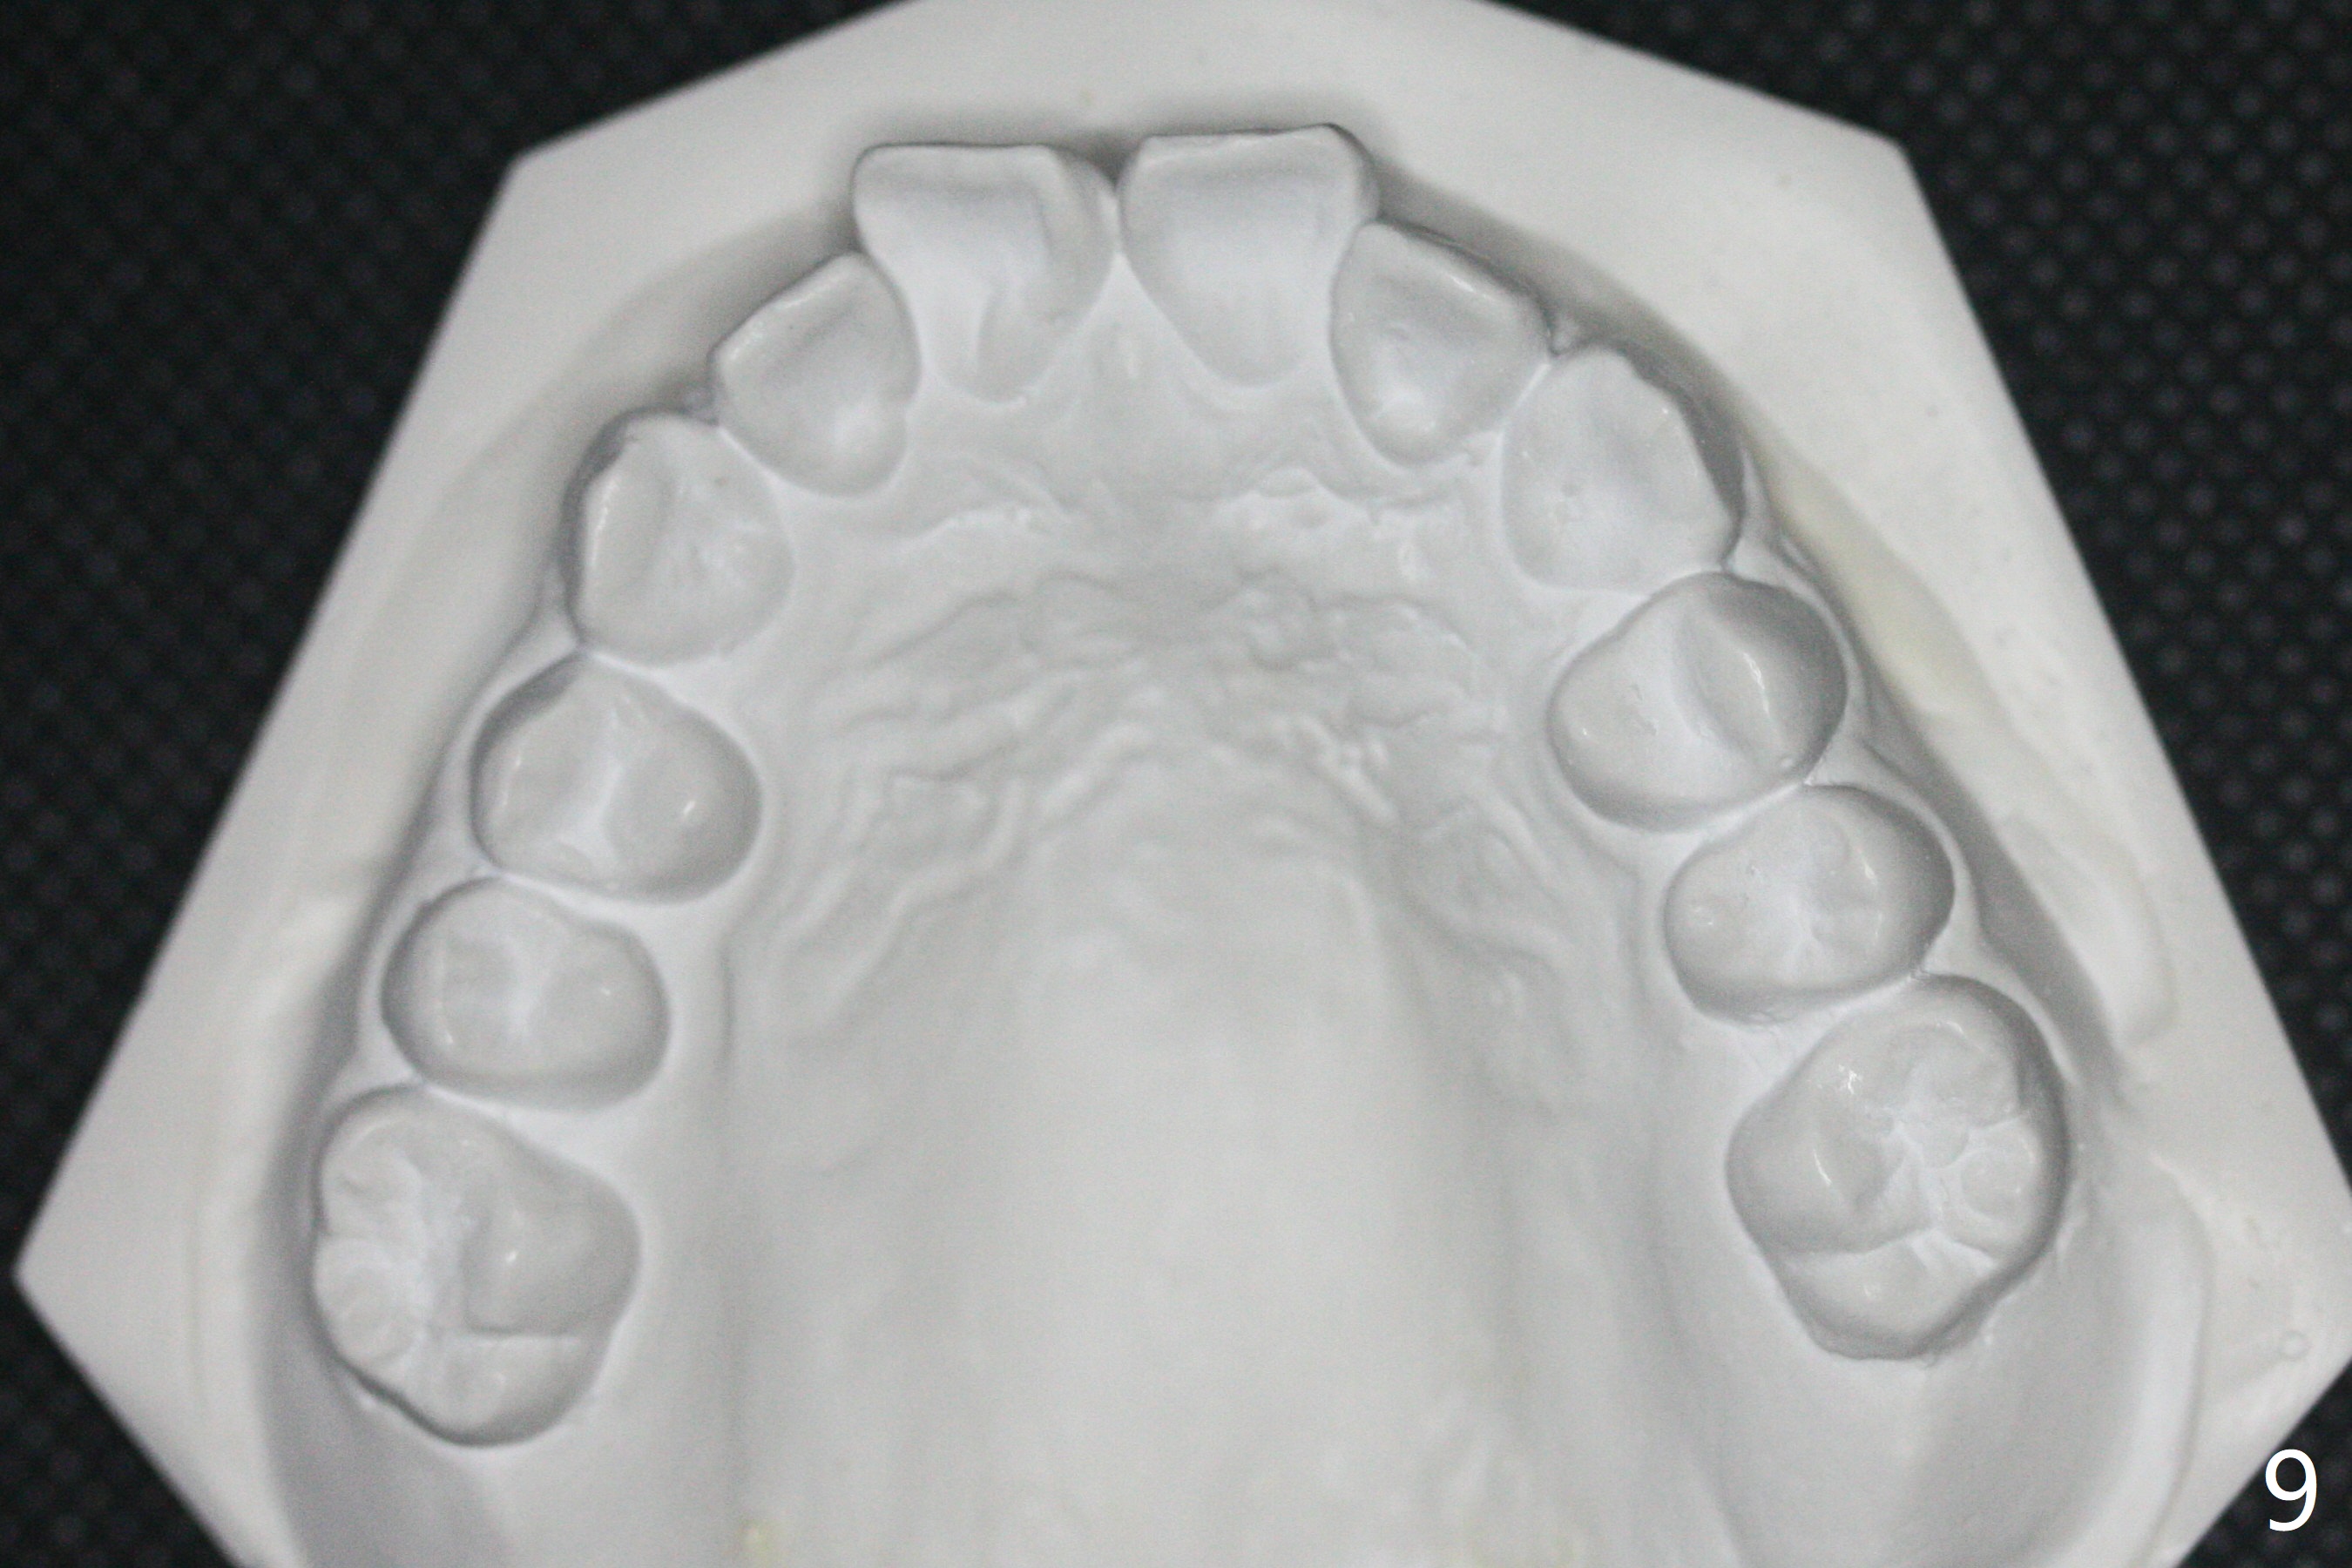

A 12-year-old woman has Class I facial profile (Fig.1-4,12,13) and apparently Class II Division I malocclusion (Fig.6-11). Start Class II retraction as early as possible to take advantage of the upper and lower posterior diastemata (Fig.9,11 (in fact there is no diastema)). LL7 impaction is noted immediately prebanding (Fig.14). Surgical access is pending.